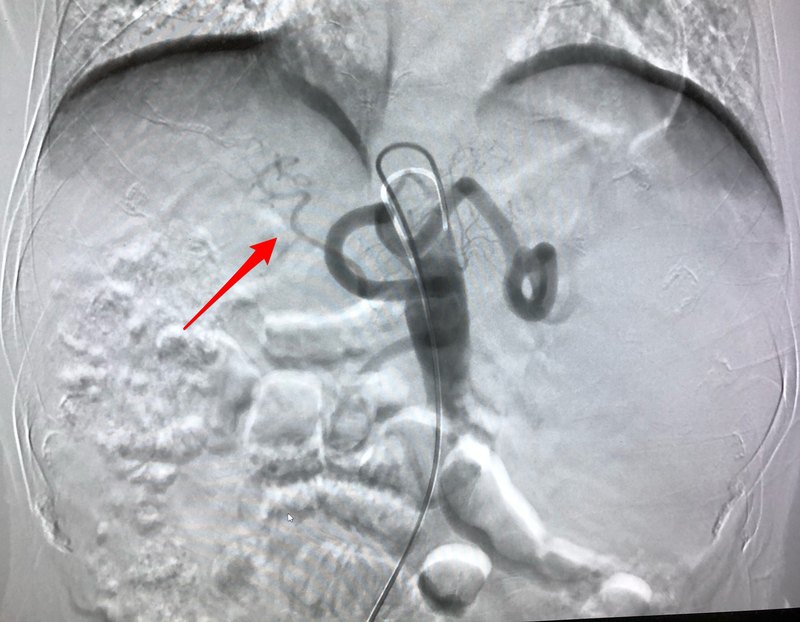

嚴重的肝硬化患者經(jīng)常伴有脾動脈盜血綜合癥,由于脾動脈增粗,肝動脈細小,肝臟有氧的動脈血供減少,最后形成脾越來越大,肝越來越小的惡性循環(huán)。這個現(xiàn)象一直沒有得到充分重視,主要是一般認為即使發(fā)現(xiàn)也無法有效干預(yù)。 常規(guī)的部分脾動脈栓塞對脾亢效果顯著,但是多數(shù)術(shù)后反應(yīng)較大,對降低門脈高壓及脾動脈盜血作用有限。我們 2008年開始開展脾動脈主干栓塞聯(lián)合脾消融治療,術(shù)后多數(shù)患者反應(yīng)輕微,不但有效治療脾功能亢進,而且可以部分糾正脾動脈盜血及降低門脈壓力,大部分術(shù)后肝功能得以改善,甚至有望部分減輕肝硬化程度。這個方案缺點是費用較常規(guī)脾動脈栓塞稍高,而且一般需要二到四次的治療才能取得滿意療效。 下面分享兩個糾正脾動脈盜血綜合癥的案例: 案例1 患者肝硬化脾功能亢進腹腔動脈造影見脾動脈明顯增粗,肝動脈細小,肝動脈分支稀疏,細小,肝臟難以得到充足的動脈血供,這可能是即使積極抗病毒治療,肝硬化仍然一直進展的主要原因。 行脾動脈主干栓塞及脾消融治療后,脾功能亢進得以部分糾正的同時,再次腹腔動脈造影,可見脾動脈血流基本被阻斷,肝動脈明顯增粗,肝動脈分支血流增加,肝臟動脈血流明顯增加。 案例2 患者肝硬化脾功能亢進行腹腔動脈造影見脾動脈明顯增粗,迂曲,脾臟血流增多。肝動脈細小,肝動脈分支稀疏,細小,肝臟動脈血供明顯不足。這可能是即使積極抗病毒治療,肝硬化仍然一直進展的主要原因。 行脾動脈主干栓塞及脾微波消融治療后,再次腹腔動脈造影,可見脾動脈血流明顯減少,肝動脈增粗,肝動脈分支血流增加,肝臟動脈血流明顯增加,對改善肝臟缺氧的狀態(tài)有顯著的意義。 脾動脈主干栓塞對糾正脾功能亢進、降低門脈壓力及糾正脾動脈盜血綜合癥意義顯著,值得大家關(guān)注。 注:做脾動脈主干栓塞及脾消融十幾年,這個方法在業(yè)界一直備受爭議,主要是很多醫(yī)生未能充分理解脾動脈盜血的危害及糾正脾動脈盜血給患者帶來的獲益。